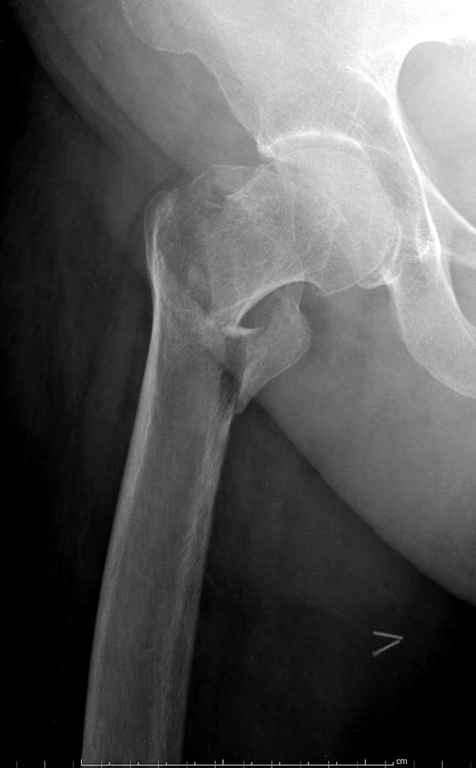

До выхода блокируемых гвоздей для фиксации косых подвертельных переломов в основном применяли Blade Plate. За счет уникальной конструкции создавался Fixed Angled Device, который соединял головку с диафизом, минуя зону перелома.

За счет особой конструкции клинка и подпорки (buttress) в диафиз создавалась стабильность, и предупреждалось скольжение по линии перелома. Перпендикулярная поверхность клинка предупреждала сгибательные и разгибательные смещения, и в сравнении с круглым винтом редко происходило прорезыванием.

В данном случае в головке бедра и в вертлужной впадине огромный дефект, навряд ли удалением импланта или заменой на другой можно сохранить сустав.

Вашему вниманию представляется похожий случай, пациентке 70, осложнился в течение одного месяца после операции. Ревизия с заменой сустава, кабельная фиксация на трохантер. При установке в дистальном диафизе обнаружен тонкий кортикальный слой и сделана профилактика от возможного перелома аллографтом.